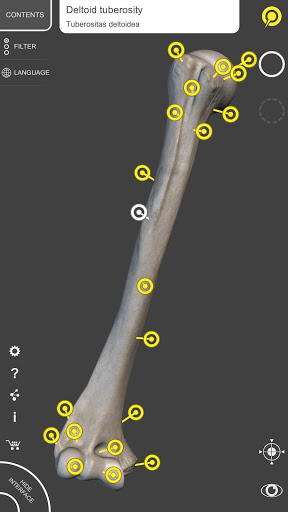

Mỗi xương của bộ xương người đã được tái tạo ở dạng 3D, bạn có thể xoay và phóng to từng mô hình và quan sát chi tiết từ mọi góc độ.

Bằng cách chọn mô hình hoặc ghim, bạn sẽ được hiển thị các thuật ngữ liên quan đến bất kỳ bộ phận giải phẫu cụ thể nào, bạn có thể chọn từ 12 ngôn ngữ và hiển thị các thuật ngữ bằng hai ngôn ngữ cùng lúc.

HÌNH GIẢI PHẪU 3D CÓ ĐỘ CHI TIẾT CAO

• Hệ thống xương

• Mô hình 3D chính xác

• Bề mặt của bộ xương có kết cấu độ phân giải cao lên đến 4K

• Xoay và Phóng to mọi mô hình trong không gian 3D

• Ghim tương tác cho phép trực quan hóa thuật ngữ liên quan đến mọi chi tiết giải phẫu